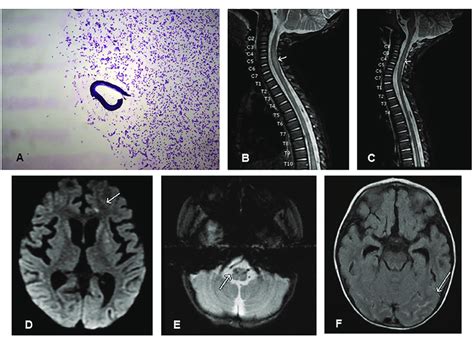

In the realm of diagnostics, CSF isofocusing serves as a valuable tool for identifying biomarkers associated with various neurological disorders. For instance, in the diagnosis of multiple sclerosis (MS), isofocusing can help detect oligoclonal bands, which are specific types of antibodies that are often found in the CSF of MS patients. The presence of these bands can support the diagnosis of MS and help differentiate it from other neurological conditions.

Isofocusing is also used in the diagnosis of meningitis, an inflammation of the membranes surrounding the brain and spinal cord. By analyzing the protein composition of CSF, clinicians can identify the presence of infectious agents, such as bacteria or viruses, and determine the appropriate course of treatment. In addition, CSF isofocusing can aid in the diagnosis of neurodegenerative diseases, such as Alzheimer’s disease and Parkinson’s disease. Changes in the levels of certain proteins, such as amyloid-beta and tau, can be detected using isofocusing, providing valuable information for early diagnosis and disease monitoring. These applications highlight the crucial role of CSF isofocusing in improving the accuracy and timeliness of neurological diagnoses.